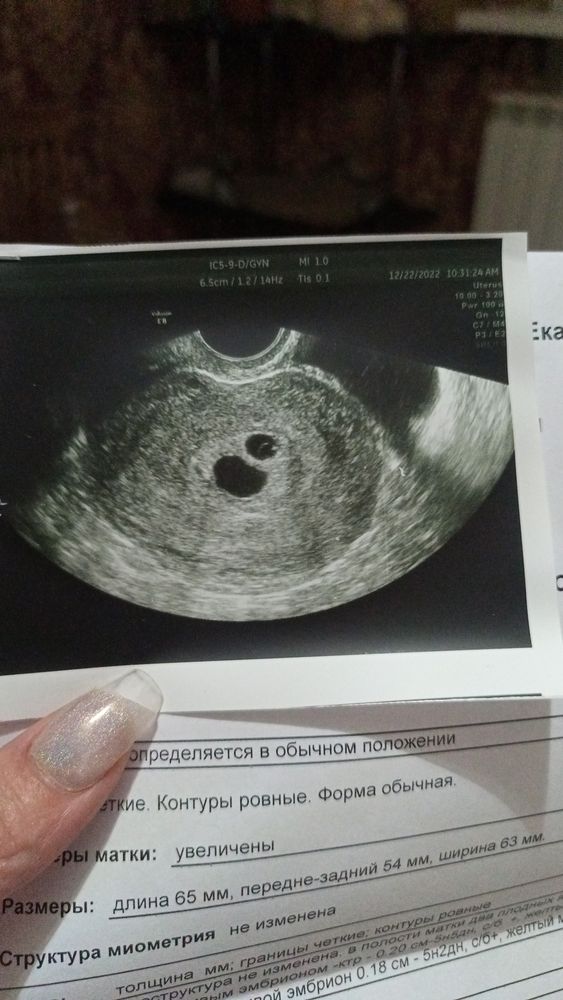

Разглядываем тесты // пока ждём результат ХГЧСегодня сдала хгч - 131 , не маловато для двойни на 9дпп?

вообще не могла глазам своим поверить что положительный результат пришел ) буду еще сдавать на 11дпп, ре назначила узи на 16.01 это будет 20дпп , там уже что то можно будет увидеть ?

На УЗИ имеет смысл идти только при значении ХГЧ 1200-1500. При меньших значениях могут лишь написать "косвенные признаки беременности в малом сроке"

По результату больше похоже на одного, но бывают конечно и исключения, сдайте в динамике, посмотрите как растет, но точно только УЗИ покажет

У меня на 10 дпп хгч был 540. Поэтому возможно у вас один малыш. На узи на 21 дпп у меня увидели одно плодное яйцо. Поэтому возможно на узи у вас тоже все увидят